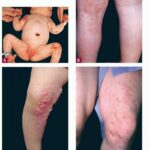

DERMATOLOGIC

The skin changes of FDH are the primary diagnostic features. There is linear, punctate, streaky cribriform atrophy with telangiectasia. The cribriform atrophy is marked by tiny ice pick-like depressions in the skin. These are distributed along the lines of Blaschko. Areas of thinned to absent dermis are irregularly distributed and the resultant herniations of fat appear as yellow-pink excrescences on the skin surface . These are easily depressed. Papillomas that may be fleshy or vascular develop throughout life and favor the perigenital, perioral, intertriginous, and mucosal surfaces.

Other dermatologic features include patchy alopecia, brittle or sparse hair, and palmar and plantar hyperkeratoses. Some individuals have had hyperhidrosis and some have had aplasia cutis congenita.